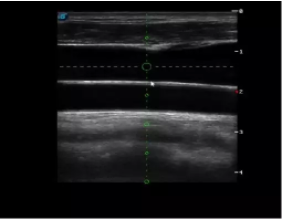

胎移植臨床圖

多數(shù)的生殖科醫(yī)生對于受精卵的植入采用憑經(jīng)驗操作或是使用傳統(tǒng)腔內(nèi)探頭引導(dǎo),同樣存在手術(shù)空間小、受精卵放置位置不確定等風(fēng)險。專業(yè)的宮腔專用探頭,配合專用的窺器使用,為醫(yī)生提供最大的手術(shù)視野。